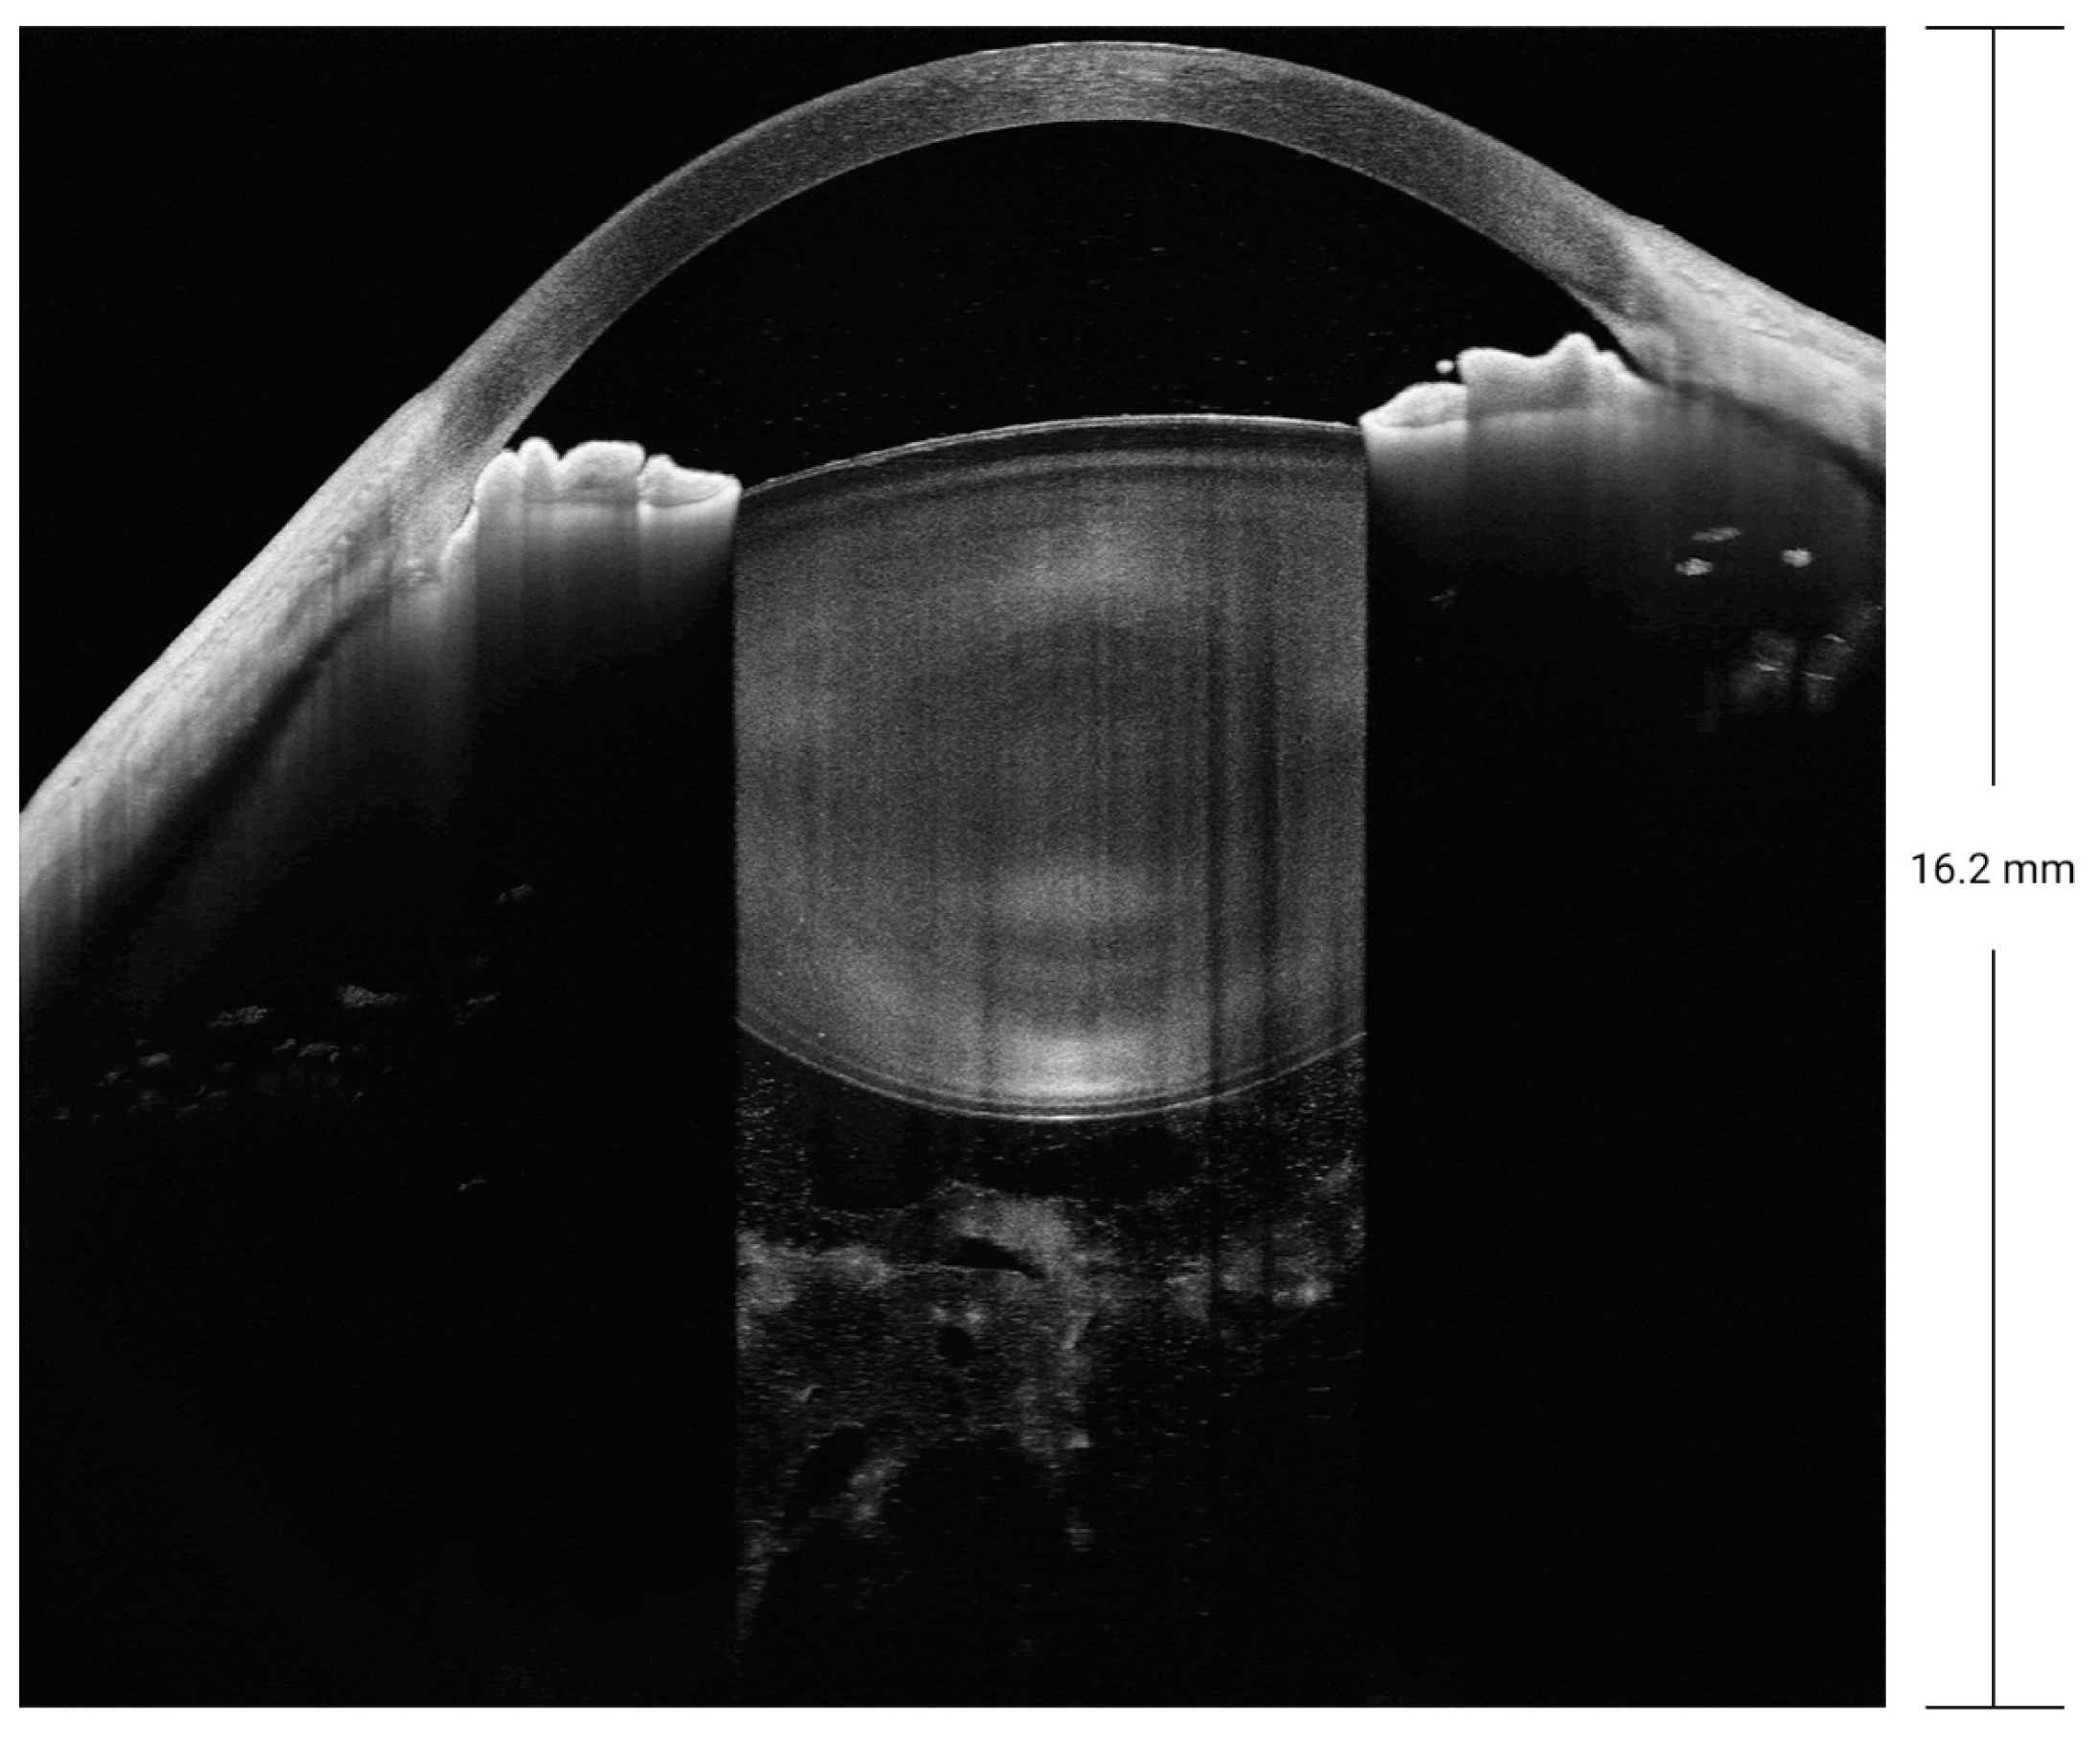

Biomedical optics requires imaging at a wavelength of 600 to 1000 nm, as tissue absorption is low within this range. SD-OCT is mainly performed at a wavelength of 800 to 900 nm. SS-OCT is mainly performed in the near-infrared radiation spectrum, at wavelengths of 1020 to 1080 nm, as the water absorption coefficient is low at a wavelength of 1060 nm [], which contributes to better imaging of tissues with a low water content. The improved penetration depth of SS-OCT with less scattering is attributable to its longer wavelength used for imaging. The images in Figure 3 were obtained for a patient with refractive medium turbidity and a macular hole. On the SD-OCT images, the retina and choroidal folds are visible over a certain range, whereas the SS-OCT images display everything from the vitreous to the choroid layer. Currently, most SS-OCT instruments are based on VCSELs, which have a coherence length exceeding 100 mm. Coupled with high-speed data acquisition, they allow steady imaging at a depth of 45 mm in tissue. Therefore, SS-OCT provides a 16 mm field of view in full-eye imaging, as illustrated in Figure 4. This is also the basis for the 3D imaging of the anterior segment.

Figure 4.

Full-eye, super-depth SS-OCT, achieving an imaging depth up to 40 mm and a 16 mm field of view. CT, cornea thickness; ACD, anterior chamber depth; LT, lens thickness; AXL, axial length; VIT, vitreous.